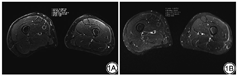

客观评价:分别测量每位受试者采用SMS采集技术的压脂T2WI TSE序列及采用PAT采集技术的压脂T2WI TSE序列的大腿肌肉信号强度(signal intensity,SI)及噪声标准差(standard deviation,SD)。将ROI放置于右侧股内侧肌中部测量SI及SD,ROI大小1 cm2 (图1),于邻近的3个层面测量3次,取平均值。分别计算每位受试者采用SMS采集技术的压脂T2WI TSE序列及采用PAT采集技术的压脂T2WI TSE序列的大腿肌肉信噪比SC,SNR=SI/SD。